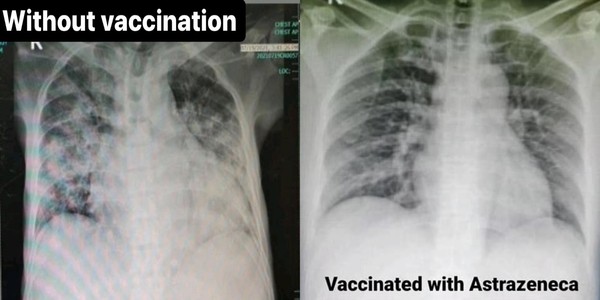

Các bác sĩ Philipines đã chụp X-quang phổi cho bệnh nhân nhiễm Covid-19, kết quả cho thấy vắc xin có thể bảo vệ phổi khỏi bị xơ hóa một cách hiệu quả. Người không tiêm vắc xin, phổi bị xơ hóa nghiêm trọng (Ảnh/Lấy từ Facebook của Tiến sĩ Anne Gabriel-Chan).

Hình ảnh cho thấy, tình trạng của 3 bệnh nhân đã được tiêm các loại vắc xin khác nhau tương đối nhẹ. (Ảnh lấy từ Facebook của Tiến sĩ Anne Gabriel-Chan)

Bệnh nhân chưa được tiêm phòng có triệu chứng xơ hóa phổi. (Ảnh lấy từ Facebook của Tiến sĩ Anne Gabriel-Chan)

Tuy nhiên, trên phim chụp X-quang của bệnh nhân thứ 4 chưa từng được tiêm vắc xin Covid-19, có thể thấy phổi của anh ta rõ ràng là bị xơ hóa, và bệnh nhân không còn thở được khi được đưa đến bệnh viện, cho thấy phổi của anh ta không còn hoạt động bình thường, cần được chuyển đến phòng chăm sóc đặc biệt với phẫu thuật xâm lấn để sống sót.